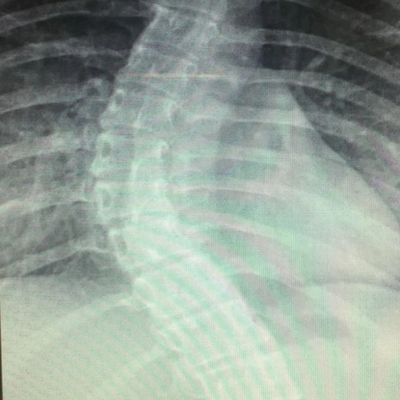

Scoliosis affects about 2-3% of people in the US, totaling around 7 million. It can start in infancy, adolescence, or adulthood, regardless of race or income. Typically, it begins between ages 10 and 15 and affects both boys and girls equally at first. But girls are eight times more likely to develop a severe curve needing treatment.